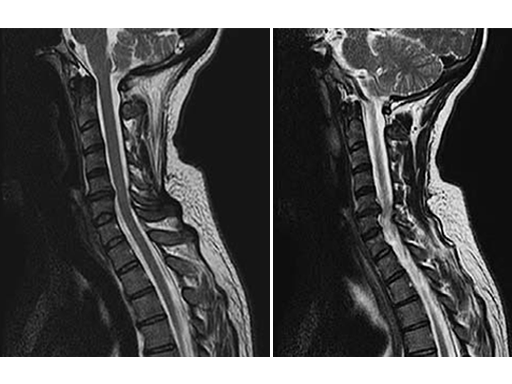

A 49-year-old woman complained of a persistent cervicobrachial pain syndrome on the right side, over a period of five years, which was refractory to all conservative treatments. The conventional x-ray of the cervical spine showed a slightly pronounced degeneration with kyphosis of the segment C5/6, and preoperative MRI showed disc protusion (fig.1).

After an uneventful surgical procedure (Fig. 2) and recovery, the preoperative pain syndrome resolved completely.